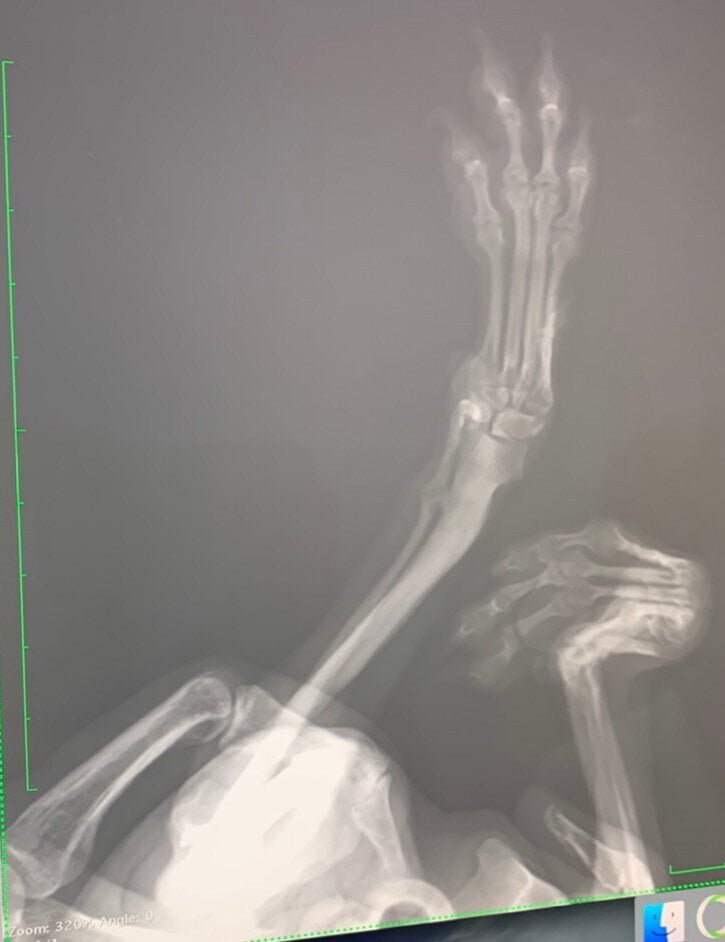

緊急保護したパピヨンの女の子ですが骨折していると言う事でした。

画像では分かりにくいかもしれませんが片足は折れてグニャグニャになっており、もう片足も折れていました。

これから両足手術になりますが片足はかなり状態が悪く骨を削って短くする大手術になりそうです。

筋肉が縮んだ状態でいた月日が長い為、筋肉が伸びない可能性があり、骨が細い為最悪の場合くっつかない可能性もあるとのことです。